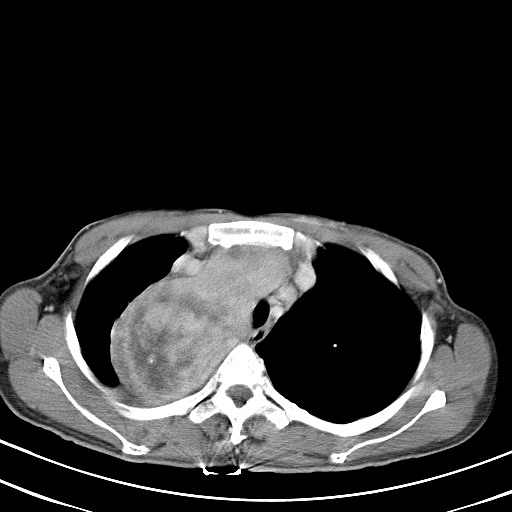

以下是引用汪涛同志在2007-8-2 0:40:00的发言:[br]病变虽然广泛,同时侵及双侧纵隔,但是无论左侧和右侧上下观察都是与右侧颈部甲状腺相延续的,而且强化幅度基本一致,又同时具有恶性病变病变的某些特征:肿块过大且密度不均,部分层面与正常纵隔结构分界不清,结合病史已有两年,考虑:胸内甲状腺肿恶变可能。[br]